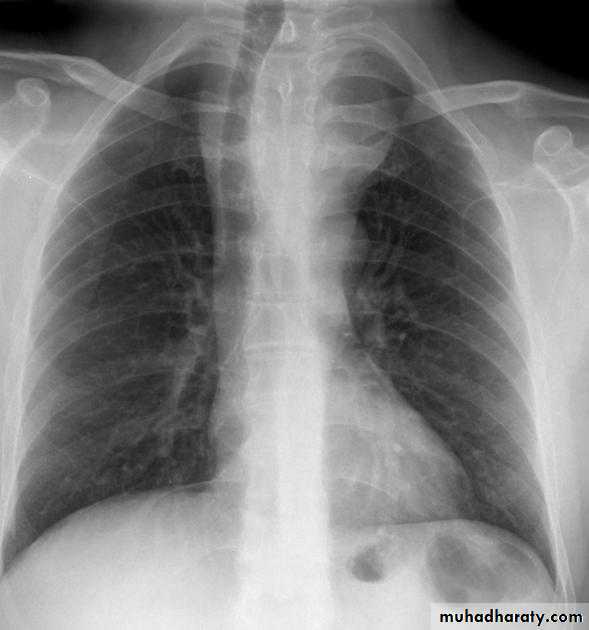

Cardiothoracic ratio (CTR) = Cardiac Width : Thoracic Width

A CTR of greater than 1:2 (50%) is considered abnormal. This however, assumes the projection is Posterior-Anterior (PA), and that cardiac size is not exaggerated by factors such as patient rotation or an incomplete breath in .

The cardiothoracic ratio aids in the detection of cardiomegaly, or more broadly,enlargement of the cardiac silhouette. .

Enlargement of the cardiac silhouette on chest x-ray can be due to a number of causes :

cardiomegaly (most common cause by far)pericardial effusion